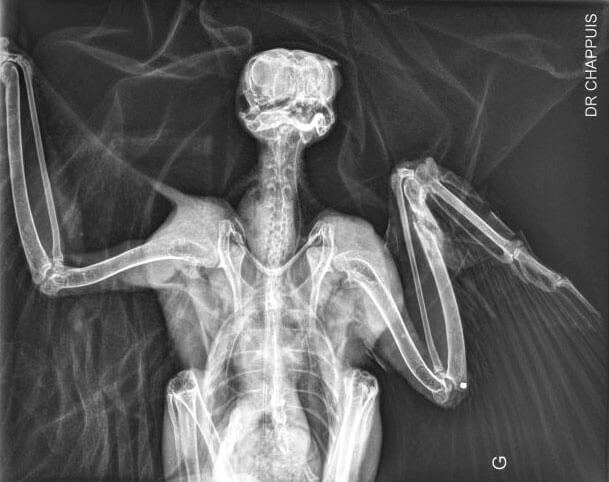

Radiographie du faucon / © Dr. Chappuis, Adrien Corsi / LPO Auvergne

L’impression 3D au secours des oiseaux - La Salamandre radiographie

Radiographie du faucon. / © Dr. Chappuis, Adrien Corsi / LPO Auvergne